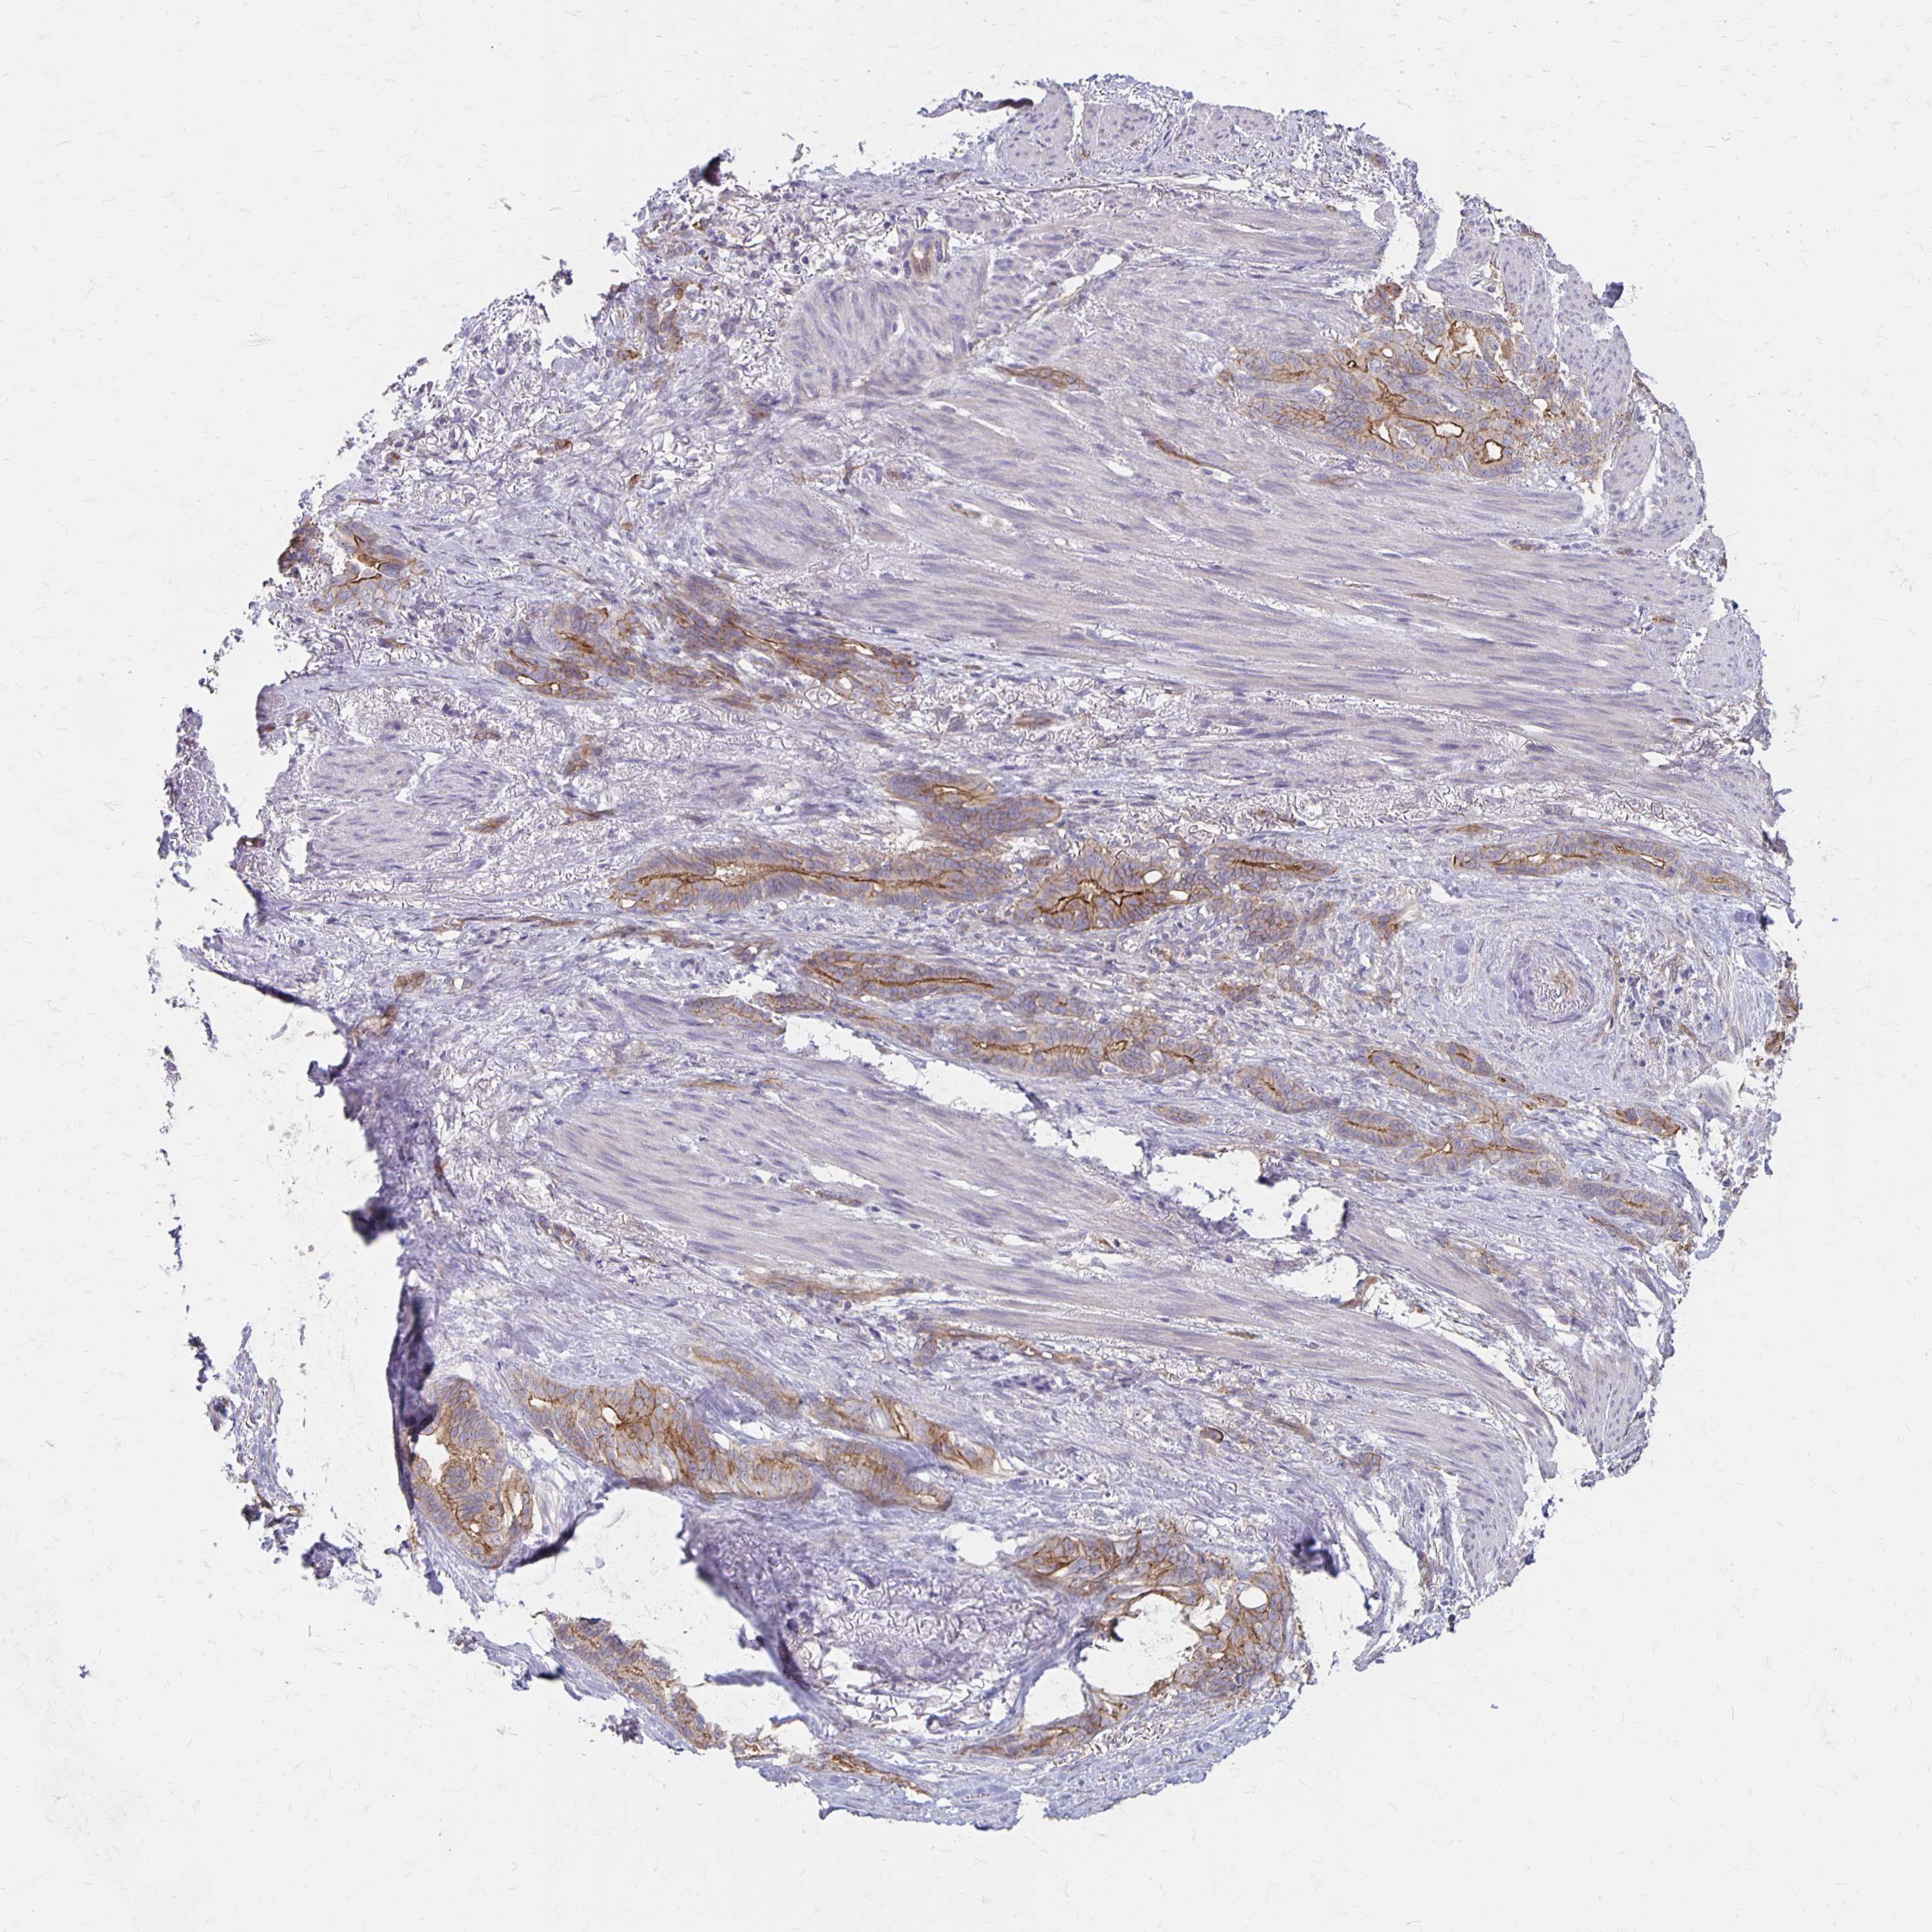

STOMACH CANCER - Protein expressioni

A mouse-over function shows sample information and annotation data. Click on an image to view it in a full screen mode. Samples can be filtered based on level of antibody staining by selecting one or several of the following categories: high, medium, low and not detected. The assay and annotation is described here.

Note that samples used for immunohistochemistry by the Human Protein Atlas do not correspond to samples in the TCGA dataset.

Antibody stainingi

Antibody staining in the annotated cell types in the current human tissue is reported as not detected, low, medium, or high, based on conventional immunohistochemistry profiling in selected tissues. This score is based on the combination of the staining intensity and fraction of stained cells.

Each image is clickable and will lead to virtual microscopy that enables deeper exploration of all samples and also displays staining intensity scores, fraction scores and subcellular localization as well as patient and tissue information for each sample.

Antibody HPA061600

Staining

High

Medium

Low

Not detected

Intensity

Strong

Moderate

Weak

Negative

Quantity

>75%

75%-25%

<25%

None

Location

Nuclear

Cytoplasmic/membranous

Cytoplasmic/membranous,nuclear

Adenocarcinoma, NOS